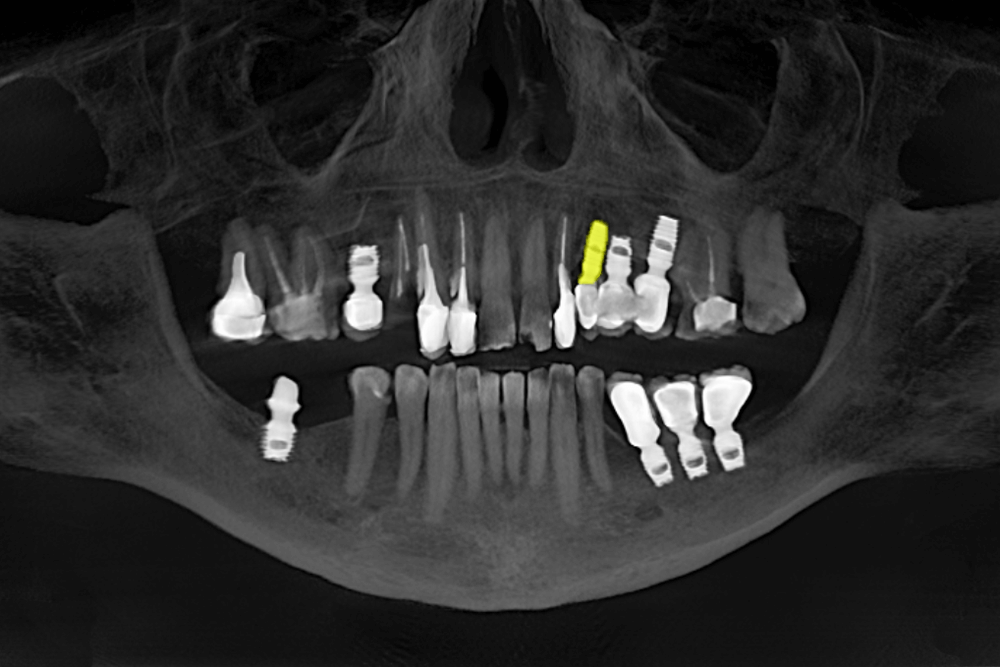

На КТ-снимке мы увидели, что один из имплантов слева на верхней челюсти не интегрировался в кость, был подвижным и спровоцировал воспалительный процесс в организме.